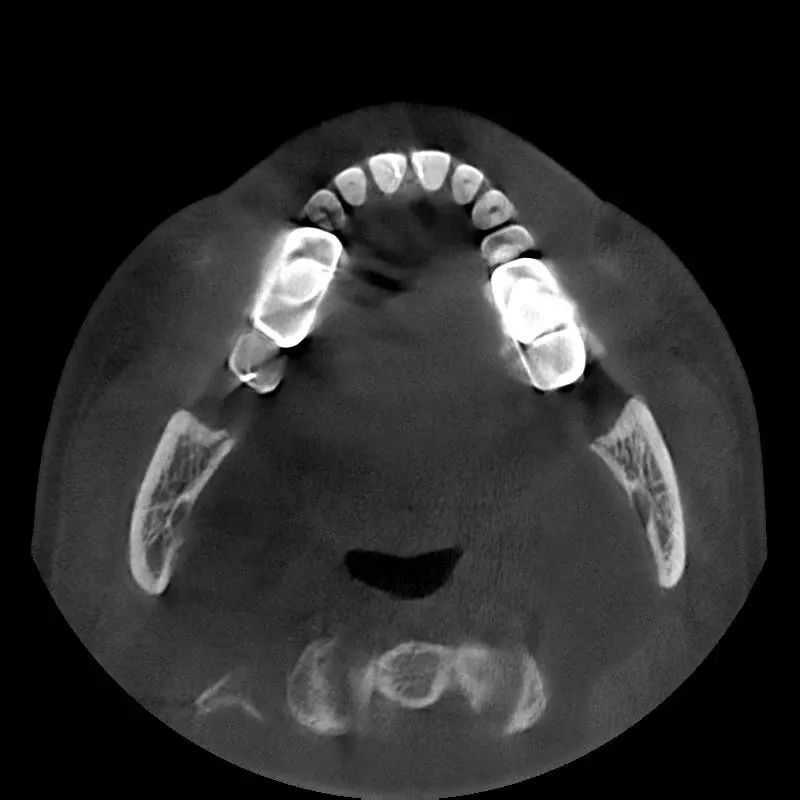

一张口腔CT的影像质量不但会影响牙科医生的临床诊断,而且还会间接影响患者的治疗效果。

每一项高端技术的突破,都如同在荒漠上开垦田地。比如,对于口腔CBCT来说,影像质量的好坏决定着市场对产品的认可度,口腔CBCT的硬件方面已趋于成熟,真正难的是软件的开发与更新迭代,研发团队成立之初就面临了极大的困境。当时国内在降低辐射剂量、金属伪影去除、超快速扫描、扩大有效视野方面都比较薄弱,难以突破核心图像重建算法,CBCT产品的影像质量一直不过关。“当时,卡脖子问题一直无法解决,压力非常大,每天都加班到深夜,有的同事甚至直接睡在公司。”CT研发总监杨振华回忆道。

影响对比